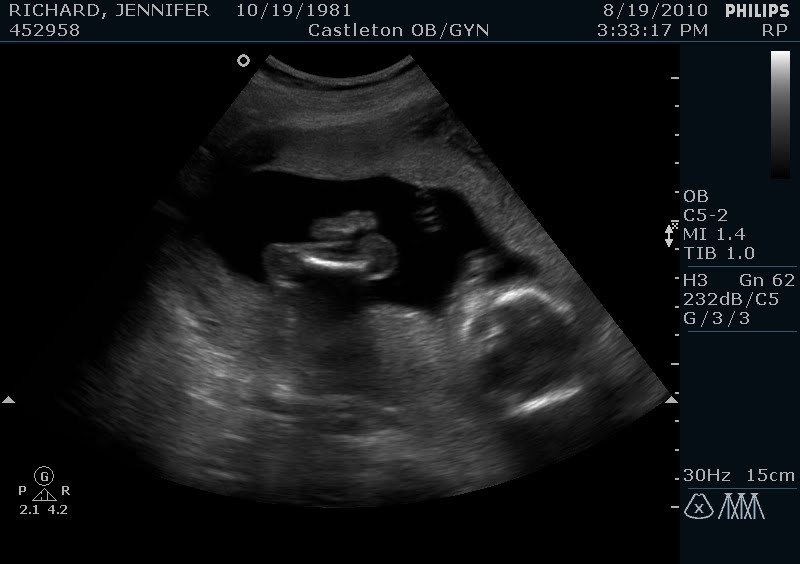

Well there is the 18 week belly for you. I feel like this weekend I am starting to look pregnant. I'm sure that's making some of yall laugh but it finally feels considerably different for me. The weirdest part though is that I am more comfortable in my regular pants now than I was a month or so ago. I guess the early bloating is gone and what I have is now all baby (and all that comes with that). My doctor said last week that she thought she wouldn't see me in regular clothes at the next appointment though. I think she's probably right. And speaking of appointments TWO DAYS till the big ultrasound!!!